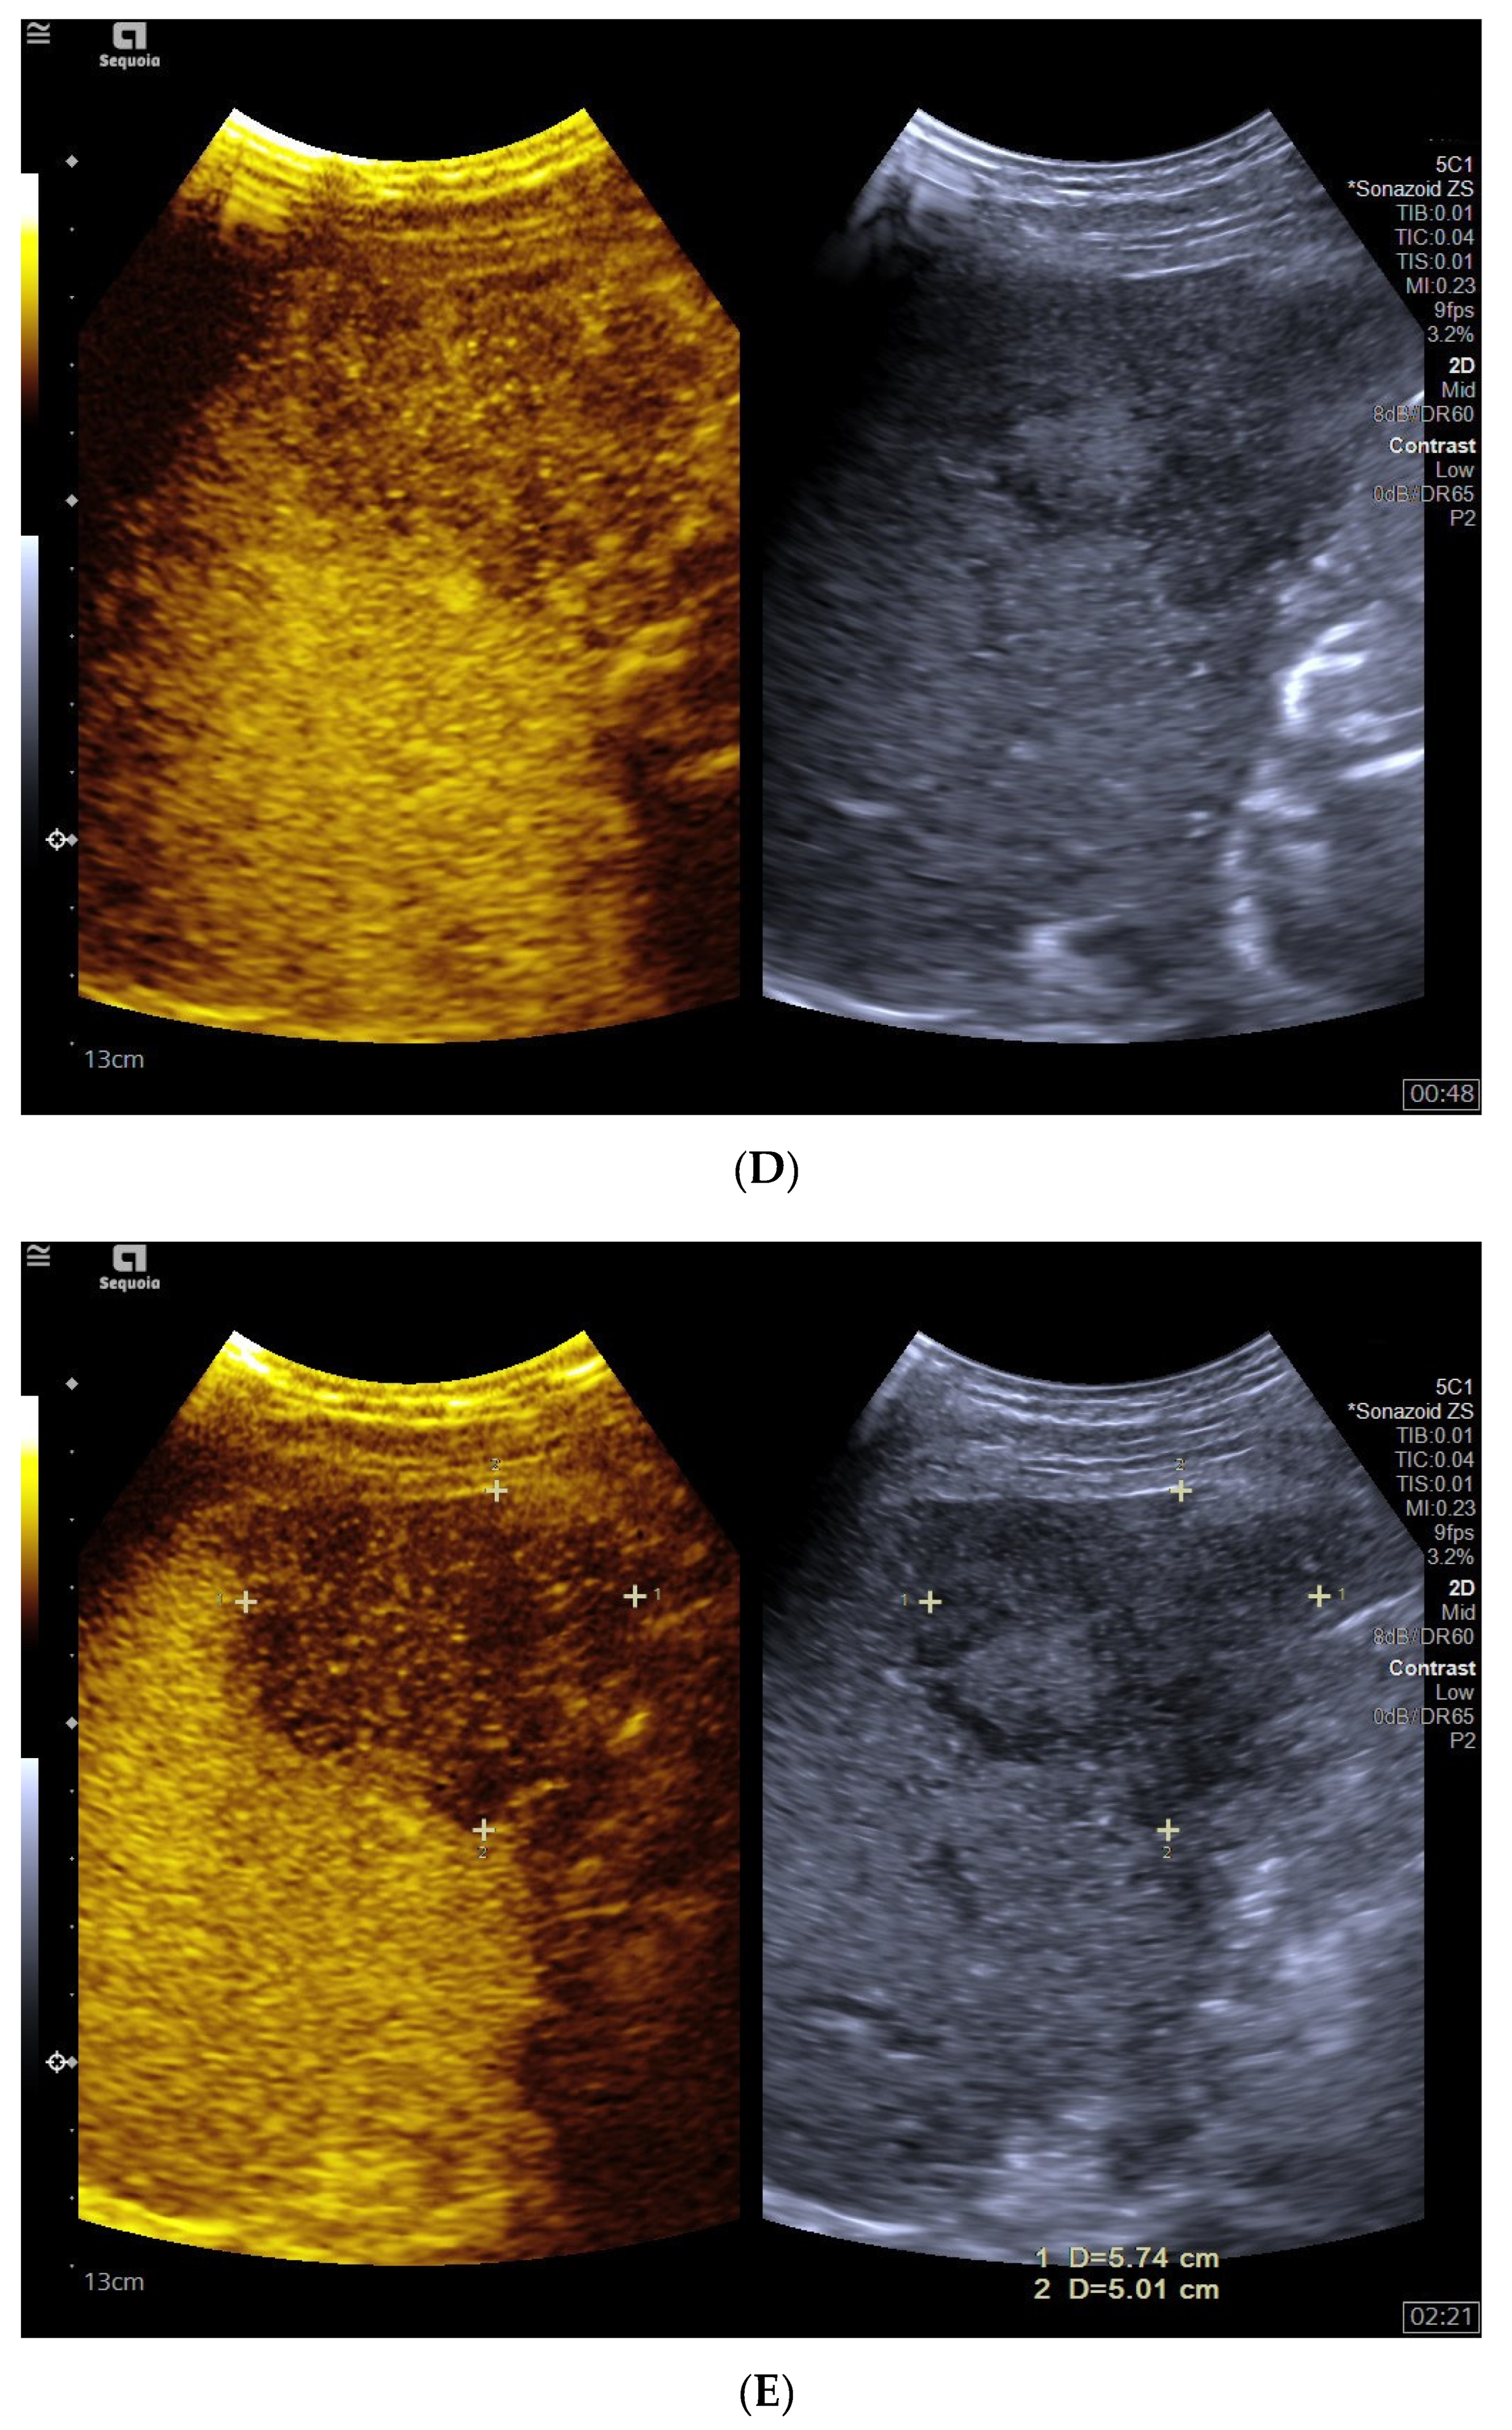

3.4. CEUS Features

3.5. Time Begin to Washout